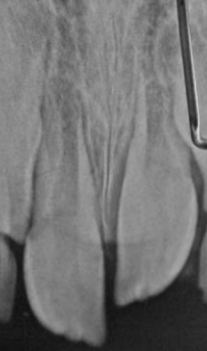

intrusion

trauma where tooth is pushed into bone

degree of trauma depends on developmental stage